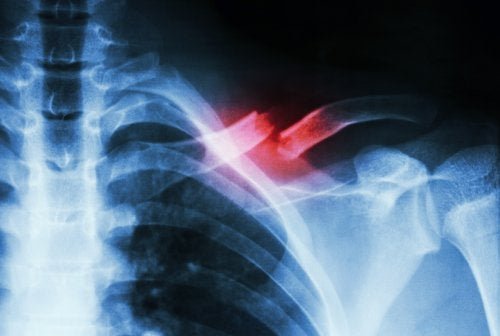

Em primeiro lugar, fala-se de fratura por estresse quando há uma pequena ruptura em um osso provocada por uma causa não relacionada a uma batida forte. Por exemplo, neste caso, a causa mais comum é a realização de movimentos repetitivos, ou o rápido aumento na quantidade ou intensidade de uma atividade.

Além disso, esses tipos de fraturas não são fáceis de diagnosticar. Requerem um especialista e exames complementares para não confundi-las com outras patologias. Ademais, isso se deve ao fato de que é comum que radiografias simples não detectem a fratura.

Em primeiro lugar, a fratura por estresse é um tipo de rachadura no osso. Esta se forma devido a microtraumautismos repetidos, ou uma sobrecarga. Manifesta-se principalmente através de uma forte dor que aparece ao fazer atividades físicas, e desaparece quando se para de realizá-las.